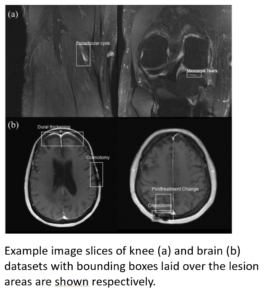

The purpose of this project is to release a set of clinically relevant labels for an existing, publicly available dataset (https://fastmri.org). With permission from the fastMRI team at NYU, we have engaged third party labelers (radiologist) to place bounding boxes on lesions in the fastMRI dataset and we would like to release those labels to the community. We intend to release the labels (CSV files) on GitHub.